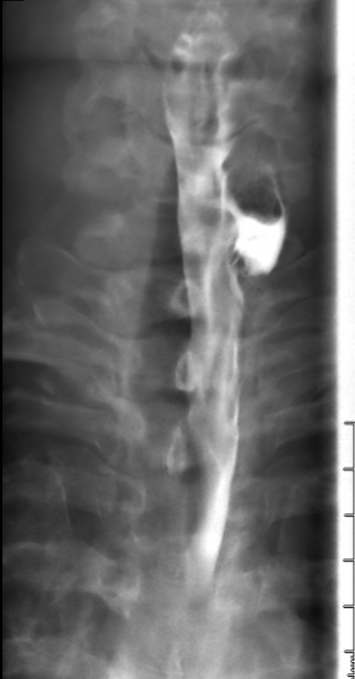

Given the significant time elapsed since her previous evaluation, our team deemed an updated EGD appropriate. On initial introduction of EGD into the inlet, a moderate-sized, Zenker diverticulum was noted (Figure 1). The rest of the esophagus and GE junction were grossly normal. After the diagnosis of Zenker diverticulum, we discussed various options with the patient, and the shared decision was made to proceed with Zenker peroral endoscopic myotomy (Z-POEM) for the definitive treatment of her dysphagia.

Figure 1: Pre-procedure esophagogastroduodenoscopy showing a Zenker diverticulum without luminal contents.

Figure 1